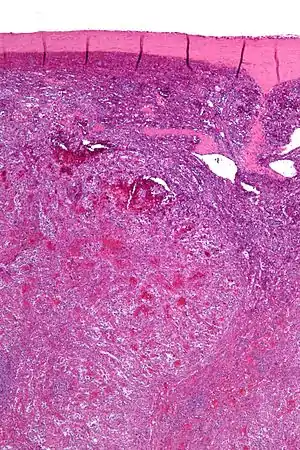

| Low magnification micrograph of a littoral cell angioma. H&E stain. | |

Littoral cell angiomas show in CT scans. They are diagnosed by pathologists by taking a sample of the tumour via Fine Needle Aspiration or Core Needle Aspiration or from a splenectomy. Histologically, they have anastoming small vascular channels and cystic spaces with papillary projections.[2]